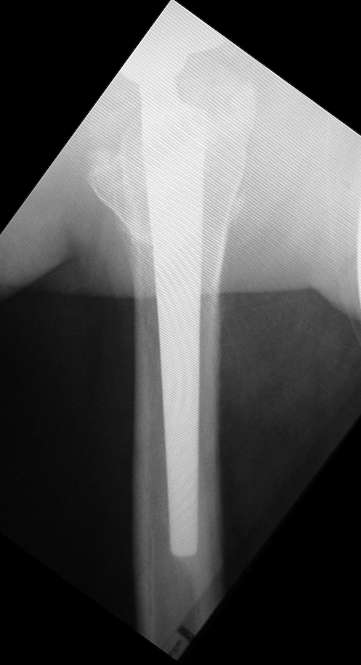

Мне кажется, что это - перипротезный остеолиз, хотя на снимке вокруг ножки явного криминала не видно. С другой стороны, если бы он был виден, то это можно рассматривать как показание к ревизии уже сейчас, а не тогда, когда случится парапротезный перелом. Я бы попробовал миакальцик. Если от него будет снижение болей (а он действует быстро, но только пока вы его даете), то тогда можно планировать более долгосрочную терапию.

Проблема не в протезе, это очень хороший протез Трилоджи-Версис ЕТ и имеются четкие признаки остеоинтеграции. Ищите другие причины болевого синдрома - тенопатия ягодичных м-ц, остеохондроз позвоночника и т.д.